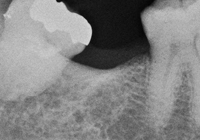

抜歯した下顎大臼歯です。2つに根が分かれています。

抜歯前にファーケーションプローブで分岐部病変を水平的に診査しているところです。残念ながらIII度でした。

抜歯後に改めてファーケーションプローブを通したところです。骨の喪失状況がわかると思います。